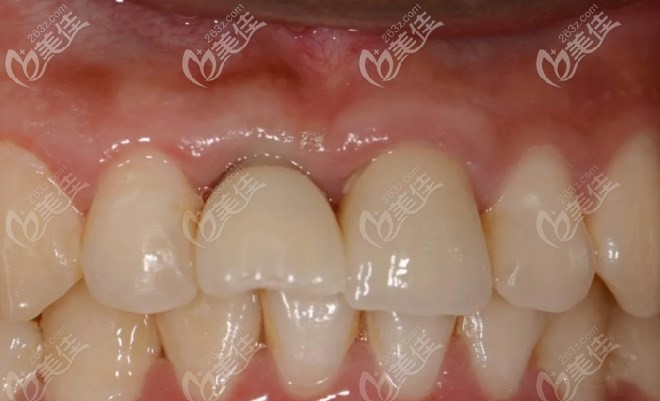

當(dāng)天種植后戴上臨時牙冠的圖片:

戴上臨時牙兩個月后復(fù)復(fù)查,無異樣后再進(jìn)行取模牙冠制作工序。

戴上牙冠后半年后復(fù)查:

你能看出來哪個是假牙嗎?從圖片可以看出種植牙不僅滿足了和自然牙齒一樣功能性還有美觀性。